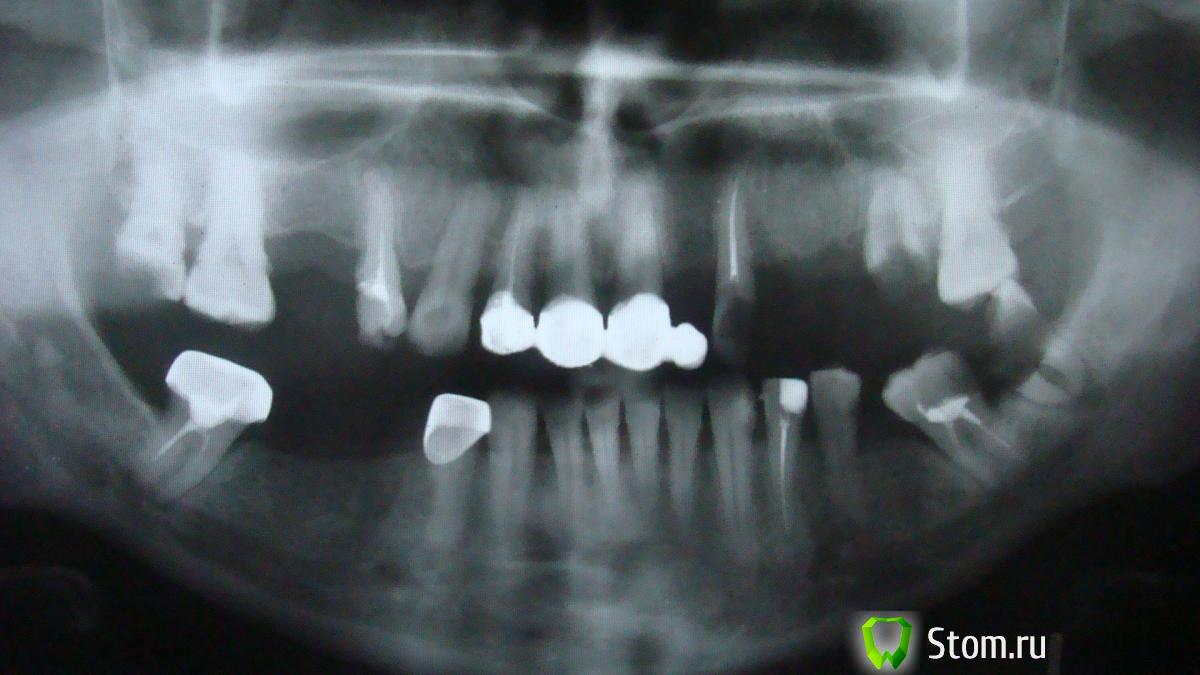

simpsons Опубликовано 15 февраля, 2012 Поделиться Опубликовано 15 февраля, 2012 Пациентка 45 лет! Планируется полная "реконструкция "Пока планируем мосты !удаление 18,27,38! Вопрос1) Можно ли готовить под опору 37(Учитывая его медиальный наклон и периодонтальное разряжение)2)мост 21, 23, 27?????? 3)Подскажите свою тактику протезирования! (учитывая импланты,пациент не слишком платежеспособный) Ссылка на комментарий

zubovolok Опубликовано 16 февраля, 2012 Поделиться Опубликовано 16 февраля, 2012 (изменено) Пациентка 45 лет! Планируется полная "реконструкция "Пока планируем мосты !удаление 18,27,38! Вопрос1) Можно ли готовить под опору 37(Учитывая его медиальный наклон и периодонтальное разряжение)2)мост 21, 23, 27?????? 3)Подскажите свою тактику протезирования! (учитывая импланты,пациент не слишком платежеспособный)1.Удалять 18,26,37,38,47.2.Лоскутная операция ,шинирование 8 нижних зубов.3.Ревизия к/к 14,12,23 зубов.4.ВКВ в 14,12,23.5.МК мостовидный протез с 13 по 23.6.Цельнолитые(бюгельные)коронки на 14,44.7.Бюгельные съемные протезы на н/ч и в/ч(в области 23 дентоальвеолярный кламер по Кемени) Изменено 16 февраля, 2012 пользователем zubovolok Ссылка на комментарий